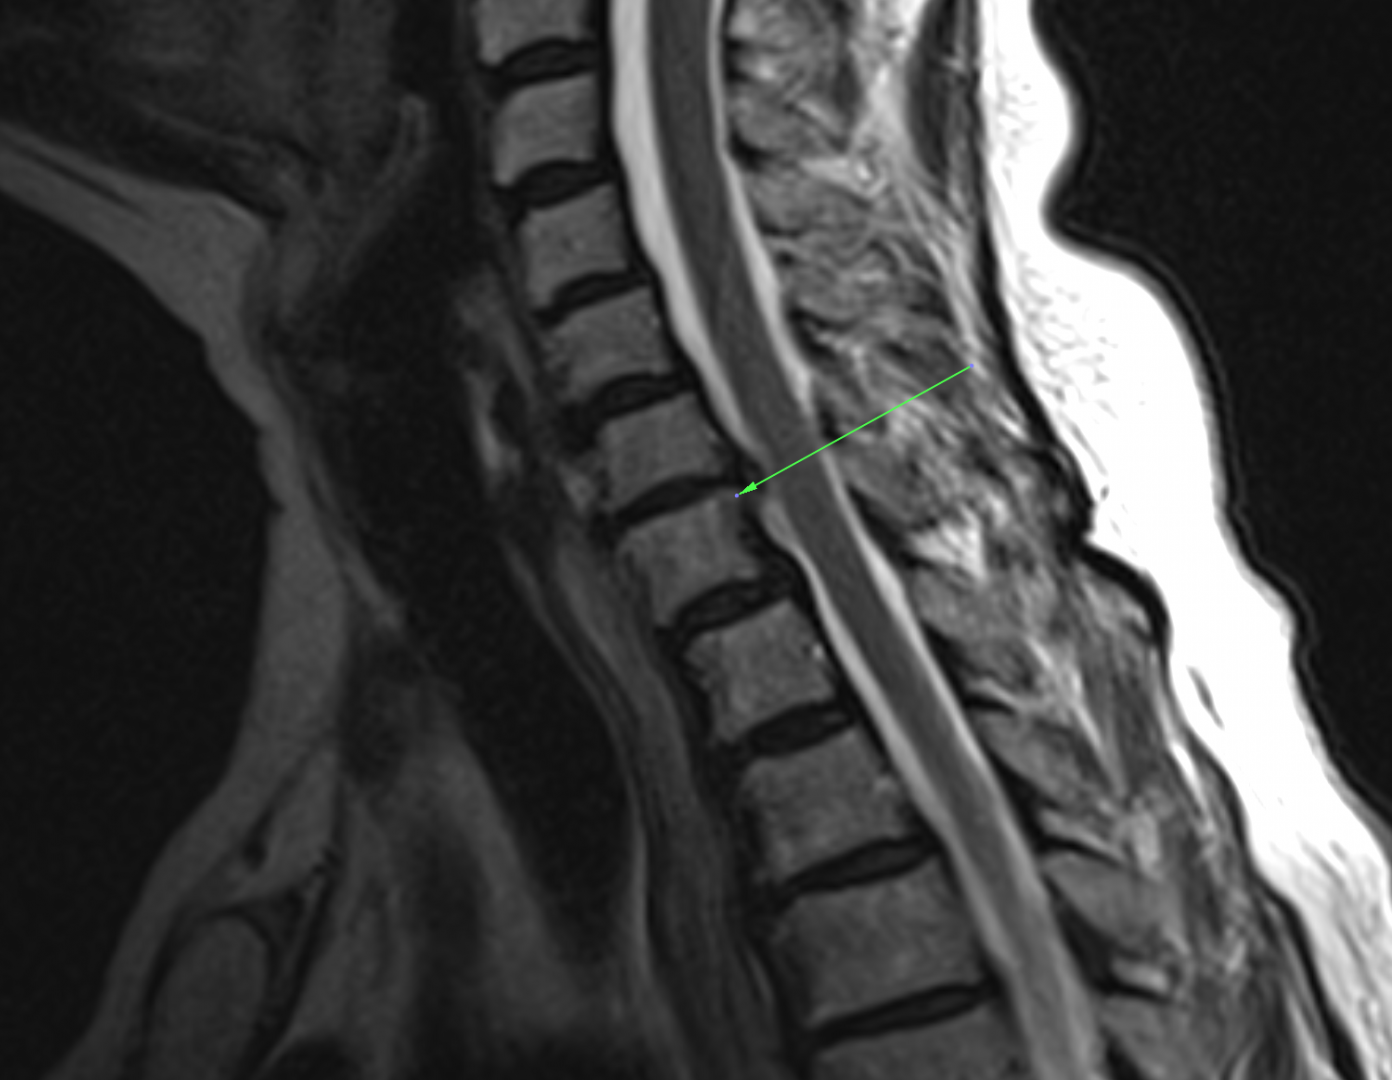

Aby wykryć guzki Schmorla konieczne jest wykonanie rezonansu magnetycznego lub tomografu komputerowego. Wówczas lekarz jest w stanie zobaczyć je jako zagłębienia w kręgach. Powstające zagłębienia mają pofałdowane ściany i są wypełnione fragmentem chrząstki oraz krążka międzykręgowego. Wskazaniem do wyżej wymienionych badań są utrzymujące się bóle kręgosłupa, niestety jak już zostało wspomniane bóle kręgosłupa mogą być przyczyną wielu schorzeń, stąd często diagnoza lekarska opiera się tylko o badanie RTG, na którym widać zmiany zwyrodnieniowe kręgosłupa.